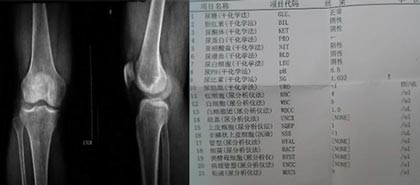

(图:王女士在我院检查时的X线片及化验单)

检查结果:体温37.2度,血沉120mm/h,类风湿因子和抗核抗体为阴性。外周血白细胞计数升高,在l0×10∧9/L(即10000/立方毫米)以上,中性粒细胞比例也明显上升,高达80~90%,有的出现核左移现象。

HD-热层析检测:患者双膝关节组织炎症明显,炎性介质体积较大,并有增多扩散趋势,需立即控制炎性病变情况。